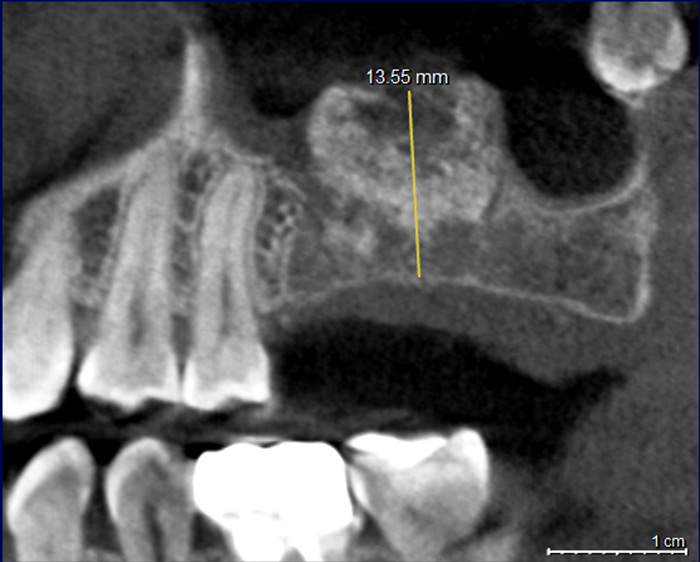

上顎骨3mm→13mmへ増やしたサイナスリフト(骨造成)症例